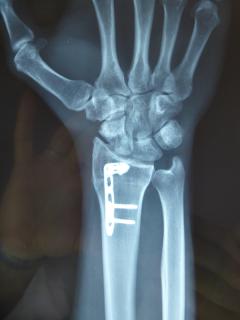

Μετεγχειρητικά 1

Μετεγχειρητικά 2

Περίπτωση 2: Μετεγχειρητικά 2